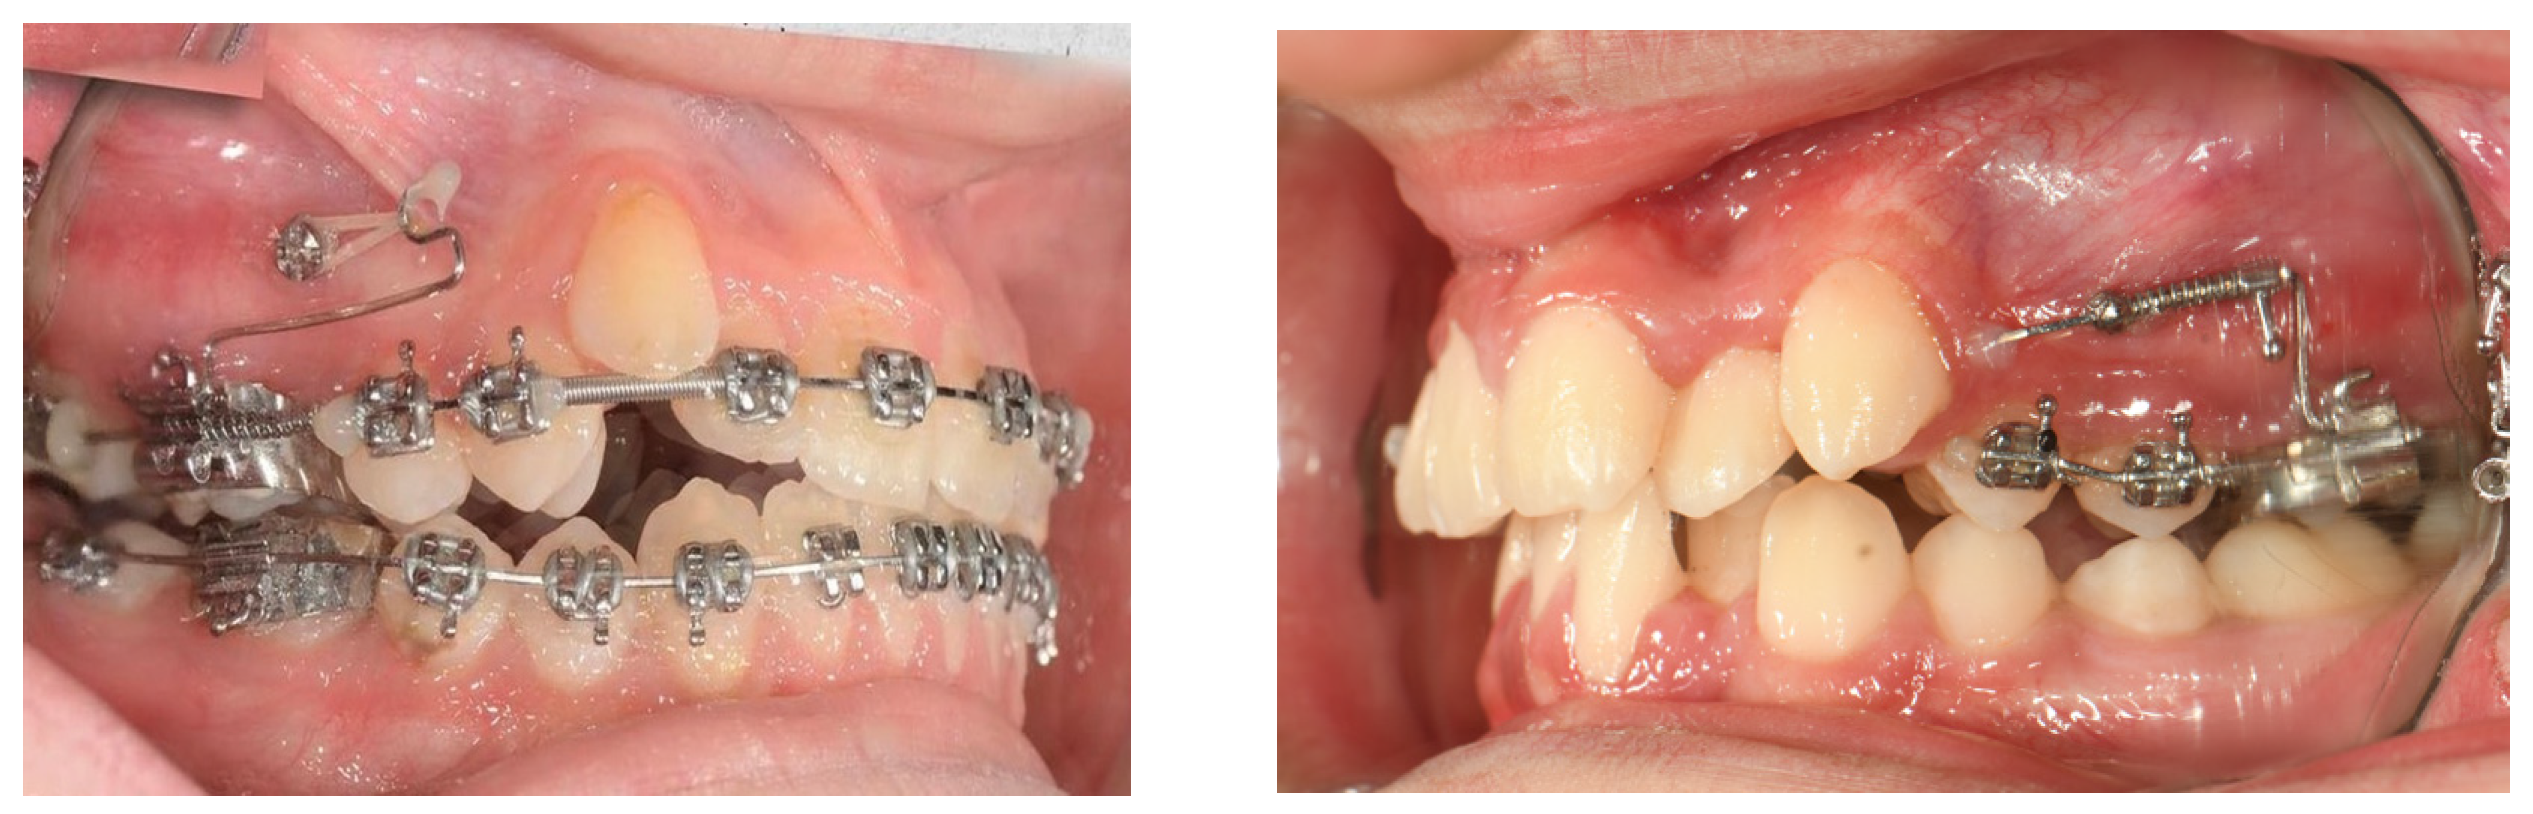

4.2.2. Buccal Miniscrew-Assisted Distalization Applications

| Bechtold et al. (2013) [58] | Skeletal supported (buccal) | Buccal miniscrew | 2.91 mm distal movement of first molars and 2.41 mm retrusion of anterior teeth | 200 g | 10.1 months | No anchorage loss | The dual-screw group demonstrated significantly greater molar distalization and intrusion, as well as incisor retraction, compared with the single-screw group. |